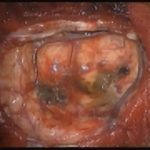

術中写真

摘出 中